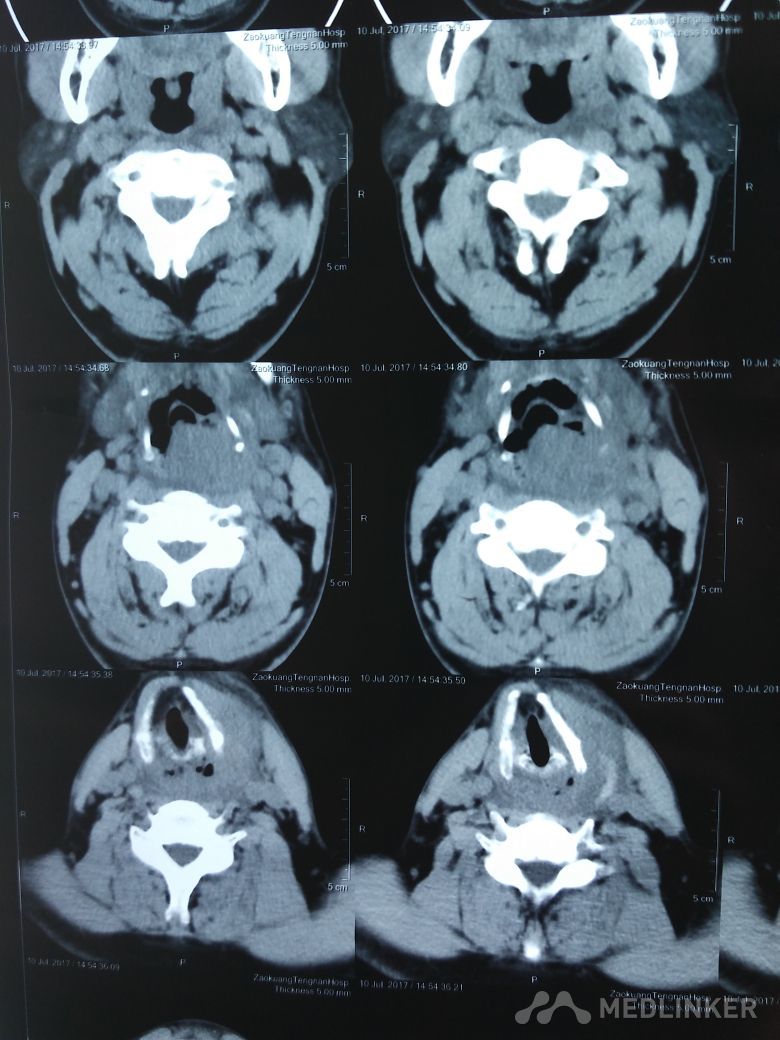

喉肿物

喉部不适半年。与半年前丝杆后部不适症状,近一个月来症状加重,并且伴有声音嘶哑,经过喉部ct检查,发现喉部新生物生长

。